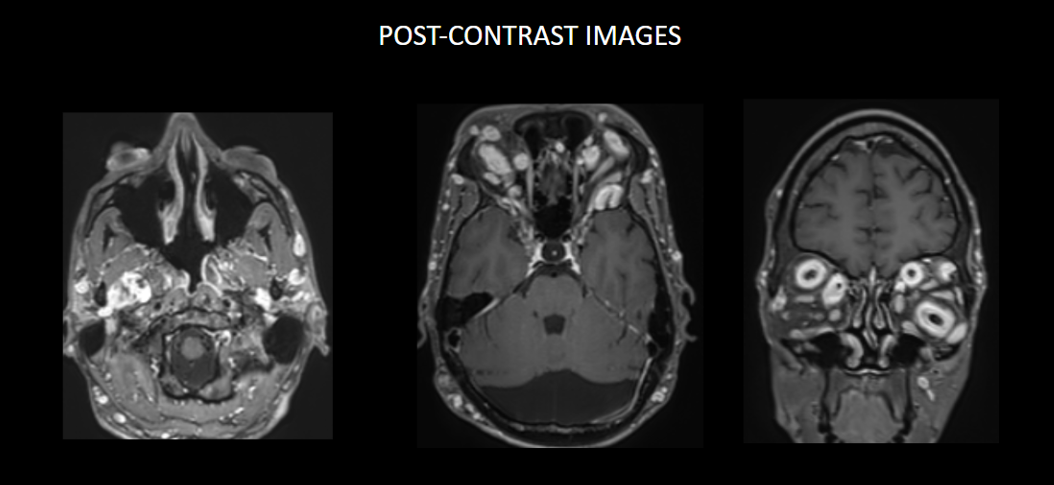

FINDINGS – MRI BRAIN WITH IV CONTRAST

Multinodular T2 hyperintense hypointense transpatial lesions seen within the bilateral orbits occupying the intra and extraconal spaces with targetoid appearance.

The lesion extends through the inferior orbital fissure into the pterygopalatine fossa bilaterally.

The lesions also extend through the foramen ovale into the superior aspect of masticator space bilaterally.

Similar heterogeneously enhancing nodular lesions are also seen bilateral fronto-temporal and occipital scalp regions. Incidental retrocerebellar arachnoid cyst.

Lesion extends into the orbital apex and along the bilateral cavernous sinuses.

Similar heterogeneously enhancing nodular lesions are seen extending into the upper neck in bilateral parotid and the visualised level II regions.

The lesions show heterogenous post-contrast enhancement.

They are best visualised on fat suppressed T2 weighted MR imaging where they appear as hyperintense masses with or without multiple target signs.

They demonstrate mild enhancement with IV gadolinium and are isointense on T1 signal.